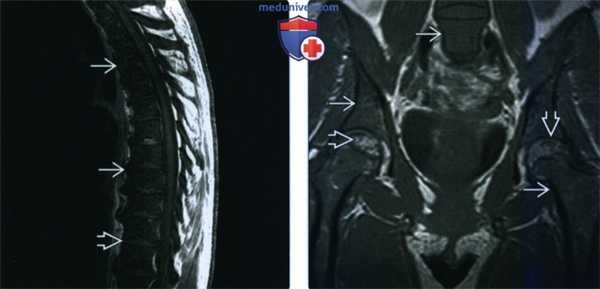

(Слева) МРТ, сагиттальная проекция, режим Т1: костный мозг характеризуется диффузным, отчетливо измененным низкоинтенсивным сигналом. Интенсивность сигнала костною мозга тел позвонков в режиме Т1 не должна быть ниже интенсивности лежащего между ними межпозвонкового диска. По результатам пункции была выявлена диффузная лейкемическая инфильтрация.

(Справа) МРТ, корональная проекция, режим TV. визуализируется диффузный сигнал, слишком низкой для 30 лет интенсив -ности. Костный мозг должен характеризоваться в большей, чем здесь, степени выраженным жировым перерождением. В структуре эпифизов визуализируется низкоинтенсивные очаги, также указывающие на вероятность инфильтрации костного мозга.

а-с Женщина 38 лет с анапластической неходжкинской лимфомой и вторичным поражением 1.3. (а) 16-срезовая КТ, сагиттальная реконструкция. Преимущественно склеротическая плотность поражения с компрессией позвонка, поражающей верхнюю замыкательную пластинку;

(b) Т1-взвешенная последовательность. Диффузное снижение МР-сигнала от костного мозга пораженного позвонка по сравнению с МР-сигналом от костного мозга здоровых позвонков. Инфильтрация тела позвонка выражена менее интенсивно в сравнении со здоровым костным мозгом,

с Т2-взвешенная последовательность. Гипоинтенсивный сигнал 1.3 вследствие формирования новой кости.